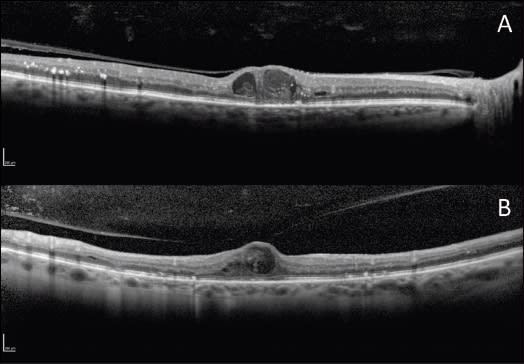

Figure 1. A. An OCT linear scan shows a thickened posterior hyaloid, diffusely attached to the retinal surface, as well as cystoid macular edema and focal disruption of the IS/OS junction. B. An OCT linear scan shows vitreomacular traction, which may contribute to the development of DME.